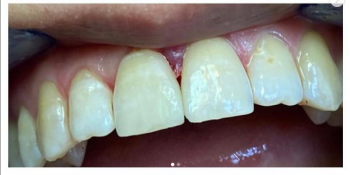

Равиля Равилевна: «Ваша улыбка – показатель здоровья и благополучия. Не даром говорят глаза – зеркало души, а зубы – зеркало здоровья. Цель моей работы – здоровые и красивые зубы пациента. А лучшая награда, когда пациент и окружающие его люди не могут отличить леченый мною зуб от родного здорового!»